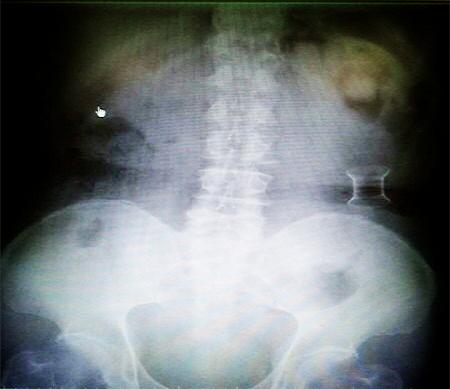

受試患者在結(jié)腸端端吻合術(shù)中,使用我司新研制產(chǎn)品達到了理想的預(yù)期效果?;颊咝g(shù)后7天、14X光片顯影,可降解腸道支架均能按研制設(shè)計的預(yù)期時間節(jié)點保持應(yīng)有強度,術(shù)后21X光片顯示可降解腸道支架已完全破碎,并排出體外。在整個試驗過程中,病患無任何不良反映,耐受良好。